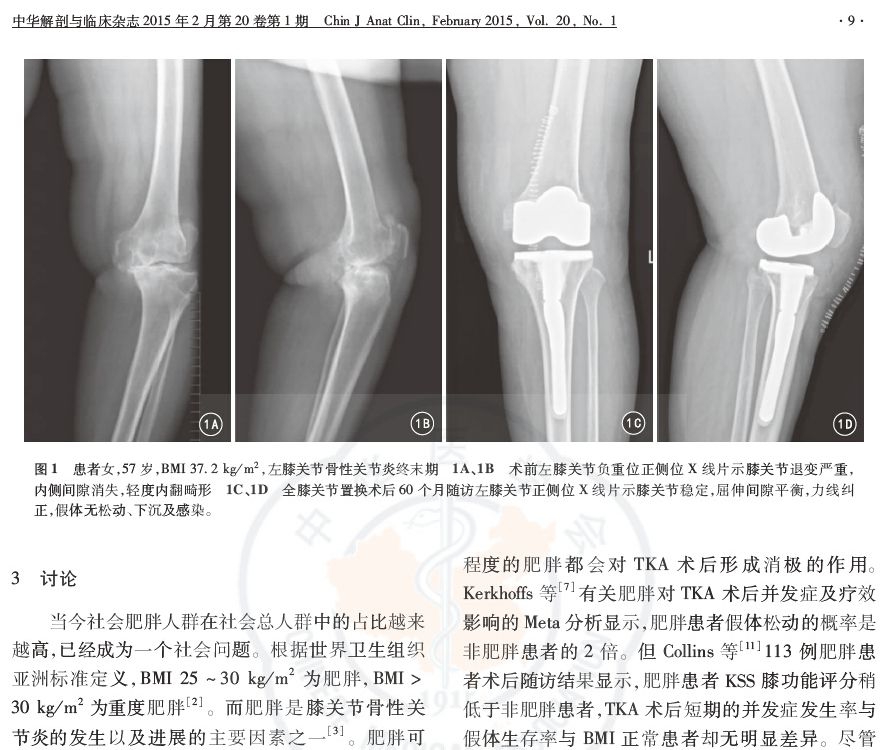

方法:回顾性分析河南省人民医院骨科2009年5月—2012年5月在初次TKA中应用胫骨延长柄治疗的19例(23膝)终末期膝骨性关节炎患者的临床资料,其中男4例、女15例,年龄53~78岁,BMI (37.7±1.75) kg/m2。单侧置换15例(左侧9例、右侧6例),双侧置换4例。应用美国膝关节学会评分(KSS)系统,记录患者手术前后KSS膝评分及膝功能评分,采用SPSS 17.0进行统计学分析,以评价临床疗效及假体生存率。

结果:17例(21膝)获得随访,平均随访44个月(27~65个月);2名患者失访。术后下肢力线良好,关节稳定,随访患者均无假体松动等相关并发症。17例患者末次随访时,21膝评分从术前的(20.8±4.5)分提高到(90.7±3.4)分,膝功能评分从术前的(25.7±4.8)分提高到 (87.0±3.7)分,差异均有统计学意义 (P值均<0.01);经侧方应力试验,17例患者均未出现内翻和外翻类型的关节不稳;未出现假体周围骨折、感染、无菌性松动、髌骨骨折等并发症,假体生存率为100%。